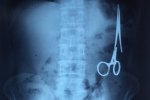

剪刀留腹中18年 越南男子手術后18年來竟無察覺異樣

剪刀留腹中18年:2016年1月2日,越南青年報報道一起醫療事故,越南鑄鋼醫院的醫生從54歲患者M.V.N腹中取出一把醫用剪刀。這把剪刀是很久前患者手術時遺留的,剪刀留在患者腹中已有18年。